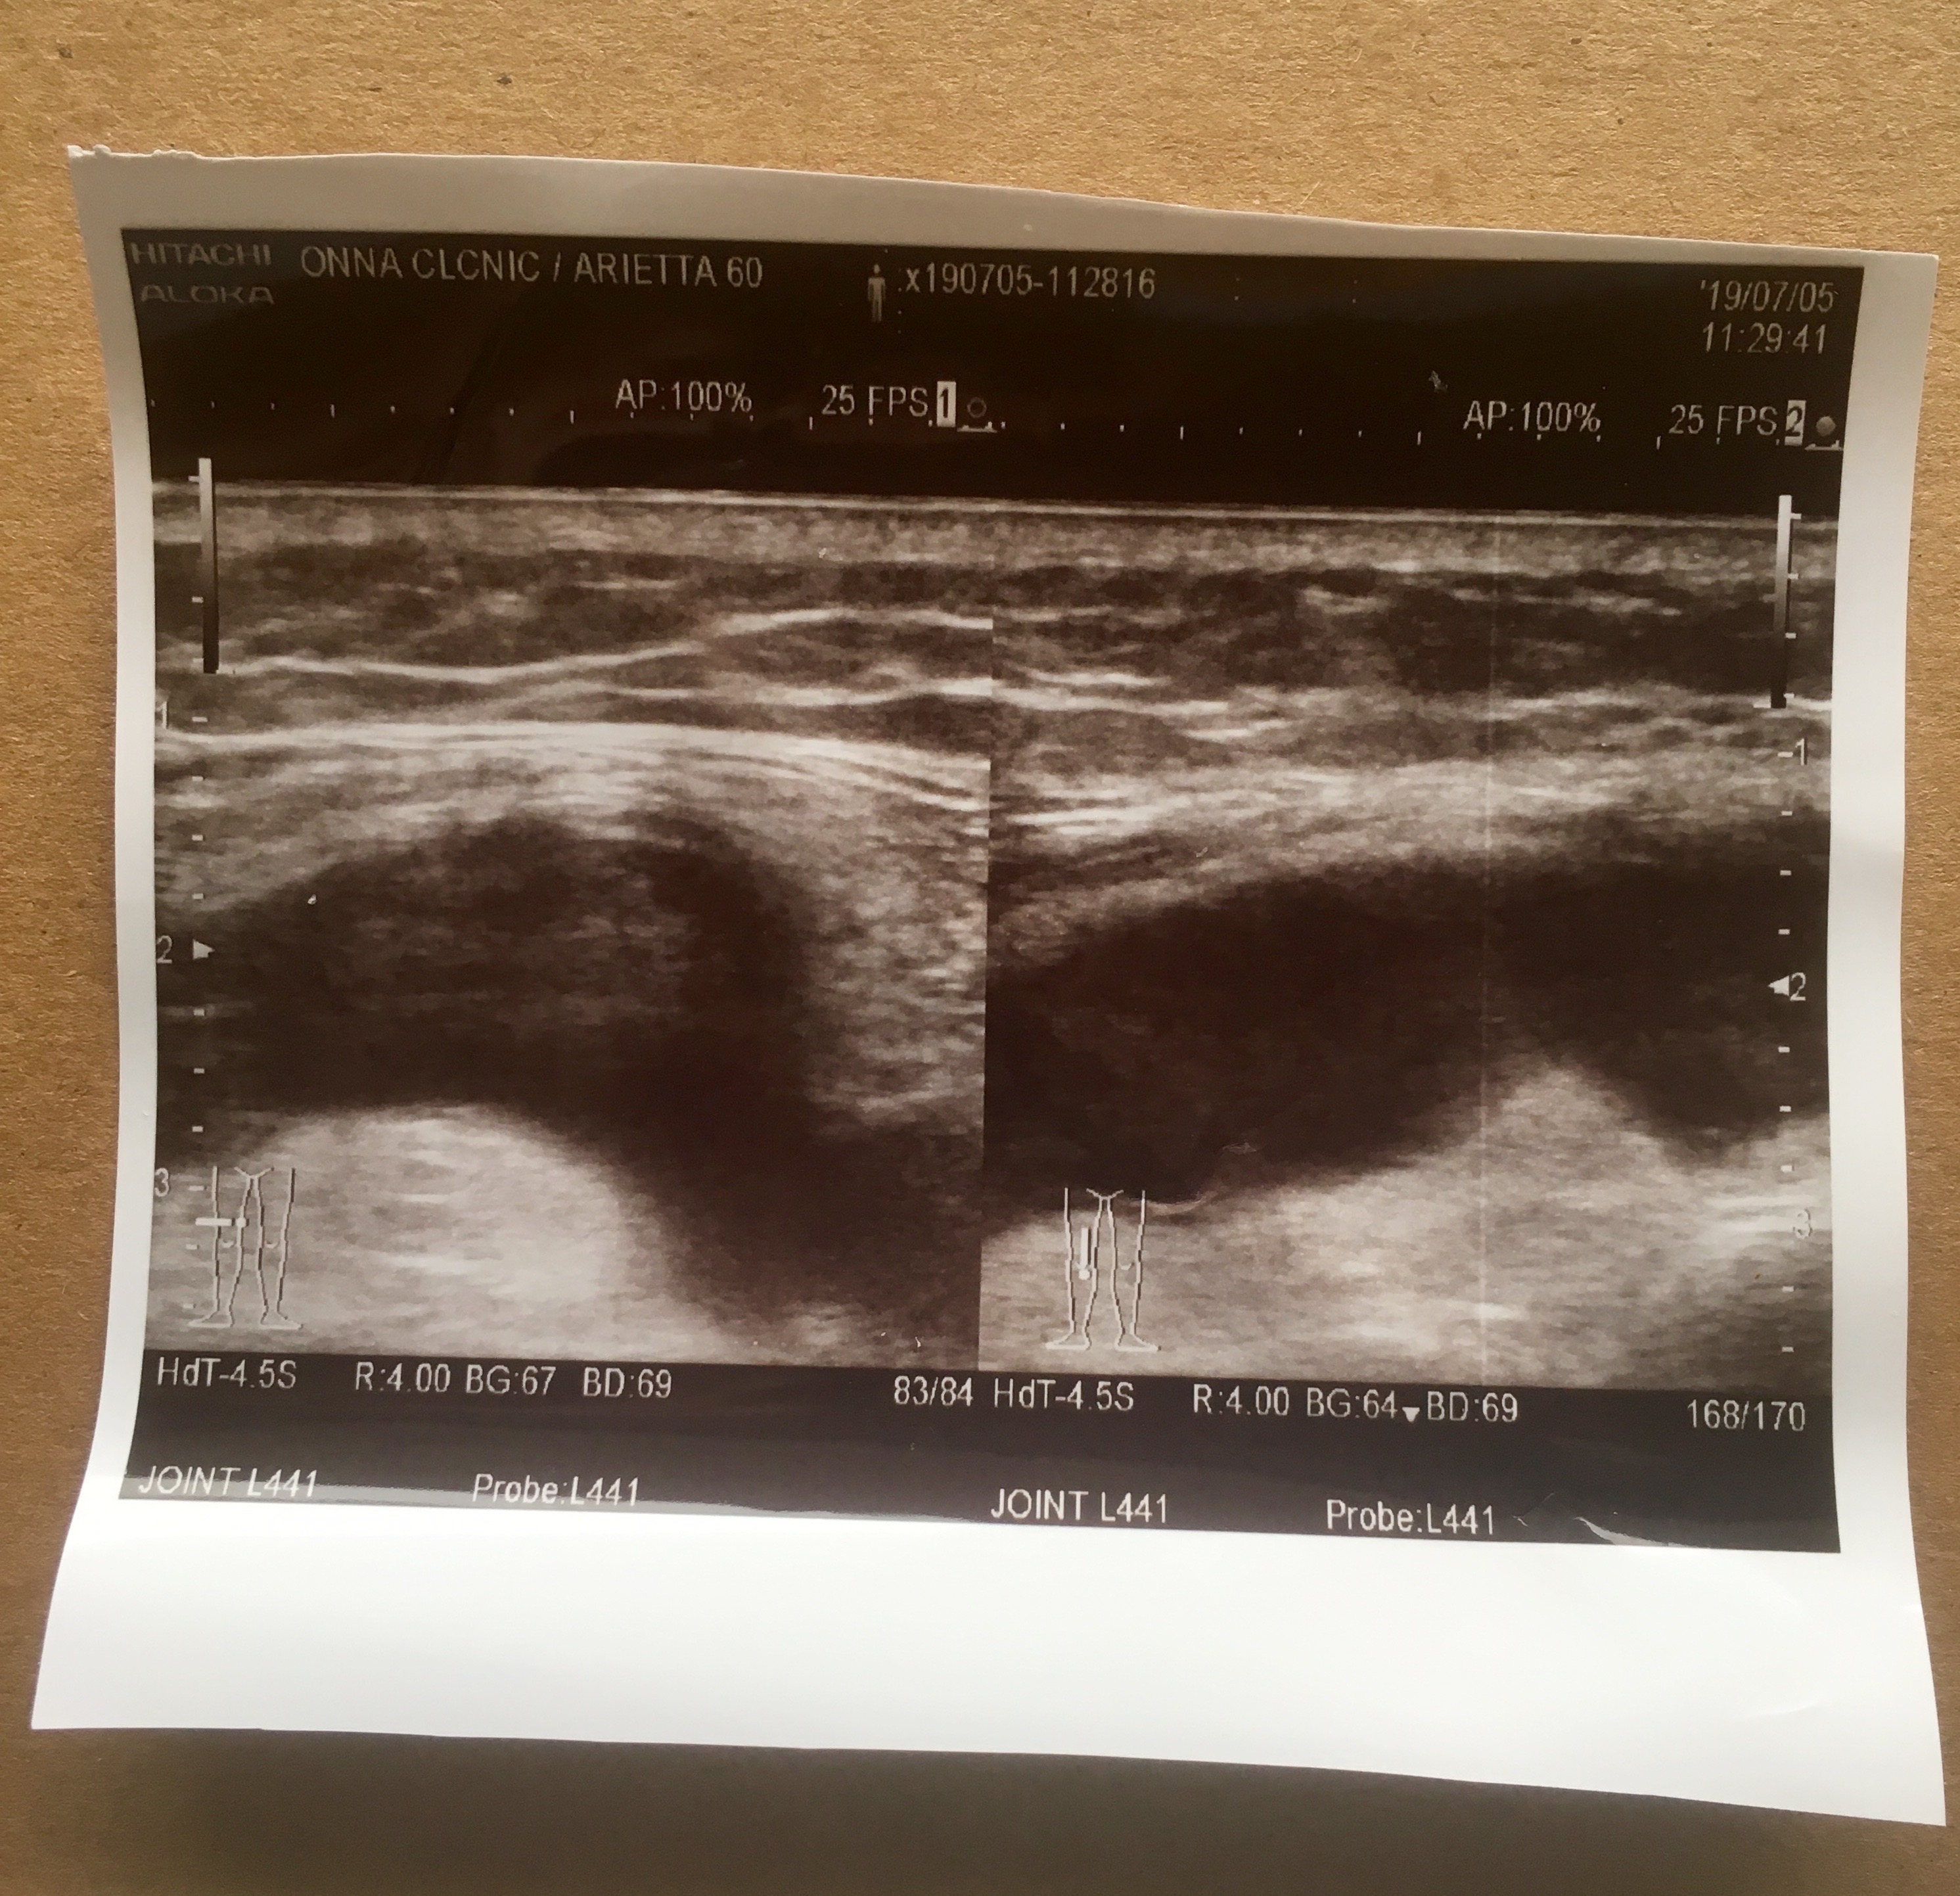

After weight, temperature, blood pressure I go to see the doctor.. He gets it immediately and says he will have to drain the liquid from my knee. I hobble into an adjoining room where I get an ultra sound scan of the knee.

The very smiling nurse give me a print from the scan, explaining that the black area is fluid and that there is a lot of it.

Hobble to a further adjacent room, laid on an operating table, the doctor gives me a local anaesthetic and then plunges a big syringe into my knee. Great excitement at the volume of fluid that is sucked out. It is a new Okinawan record of 110 mL! The doctor says something about the fluid being bloody indicating something but I do not understand.